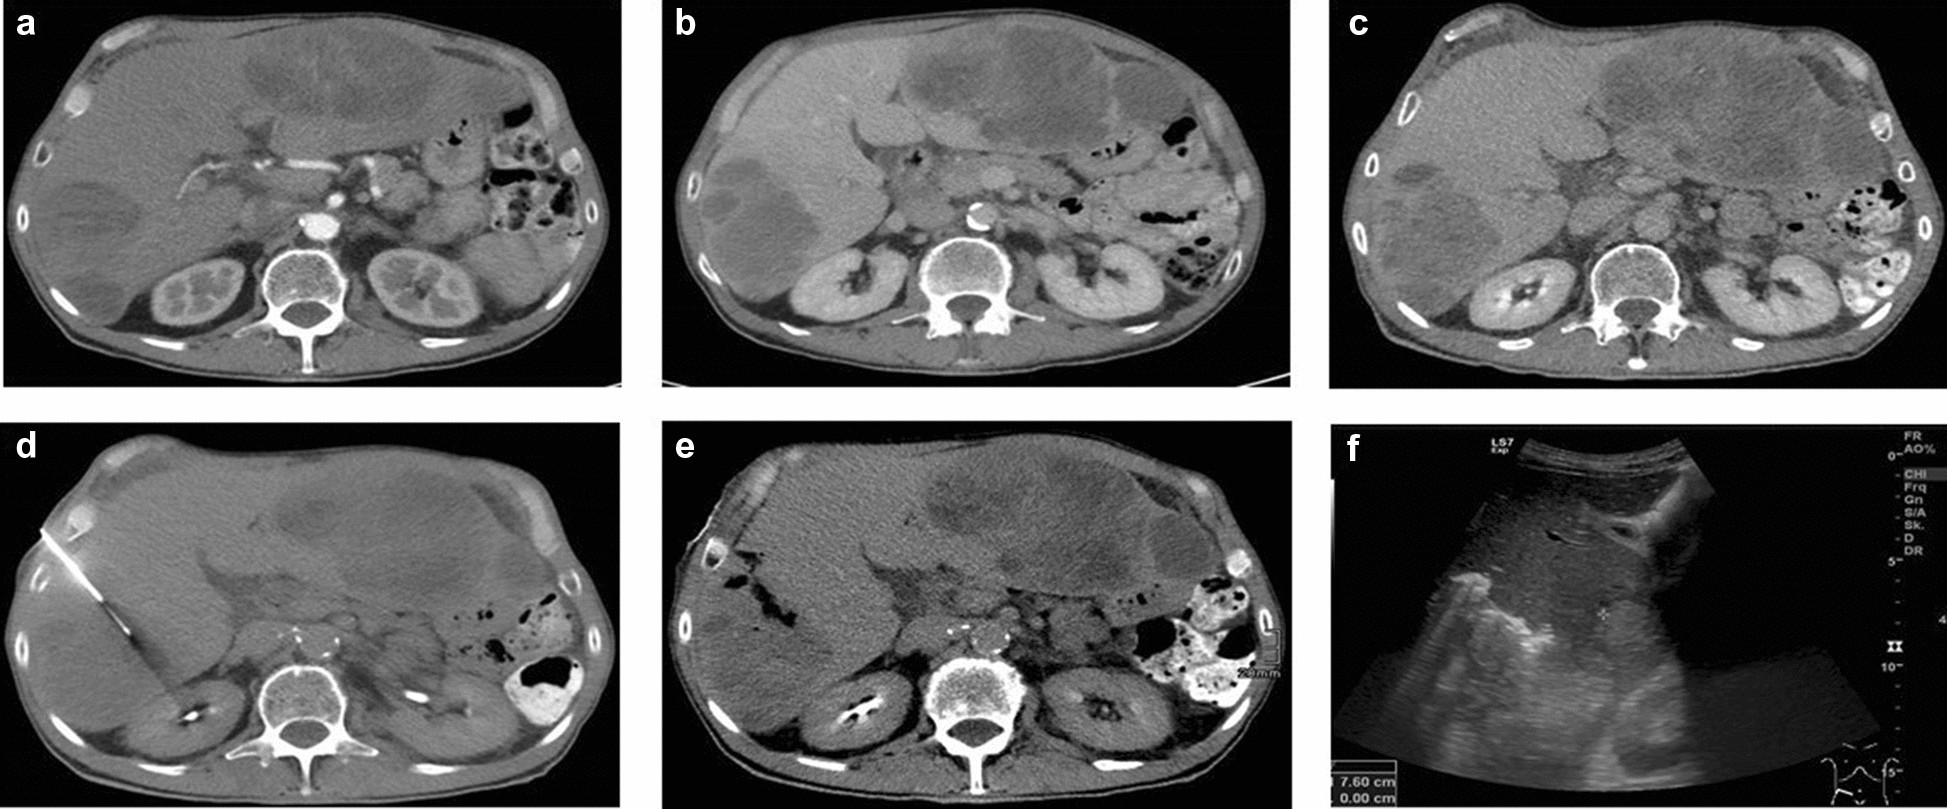

Figure 2

CT-guided liver biopsy and post-interventional sonography. (a) Axial slice of the pre-interventional CT. Target lesion in segment 5/6. Arterial phase. (b,c) Correlating axial slices of the lesion in late portal and delayed phase. Adequate biopsy tract length. (d) Biopsy performed with a 16-G core needle coaxial system and an 18-G cutting needle. Intralesional location. (e) Post-interventional non-enhanced CT. Percutaneous tract embolization by gelatin sponge slurry. (f) Post-interventional ultrasound. Adequate distribution of hyperechoic gelatin foam slurry. No ascites. No haematoma.